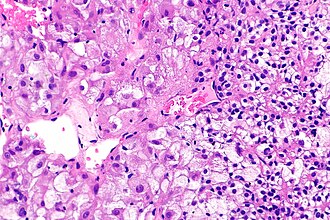

Renal cell carcinoma with morphology and IHC profile suggestive of TFEB RCC. H&E stain. | |

| LM | solid architecture with occasional rosette-like structures; two cell populations (1) large epithelioid cells with clear to eosinophilic cytoplasm, (2) small lymphocyte-like cells |

- Solid with occasional rosette-like structures.

- Two cell populations:

- Large epithelioid cells with clear to eosinophilic cytoplasm.

- Small lymphocyte-like cells.